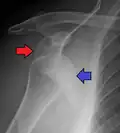

X-ray at left shows anterior dislocation in a young man. X-ray at right shows the same shoulder after reduction and internal rotation, revealing a Bankart lesion and a Hill-Sachs lesion.

In over 95% of shoulder dislocations, the humerus is displaced anteriorly.[8] In most of those, the head of the humerus comes to rest under the coracoid process, referred to as sub-coracoid dislocation. Sub-glenoid, subclavicular, and, very rarely, intrathoracic or retroperitoneal dislocations may also occur.[9]

A Hill–Sachs lesion is an impaction of the head of the humerus left by the glenoid rim during dislocation.[6] Hill-Sachs deformities occur in 35–40% of anterior dislocations. They can be seen on a front-facing X-ray when the arm is in internal rotation.[11] Bankart lesions are disruptions of the glenoid labrum with or without an avulsion of bone fragment.[12]